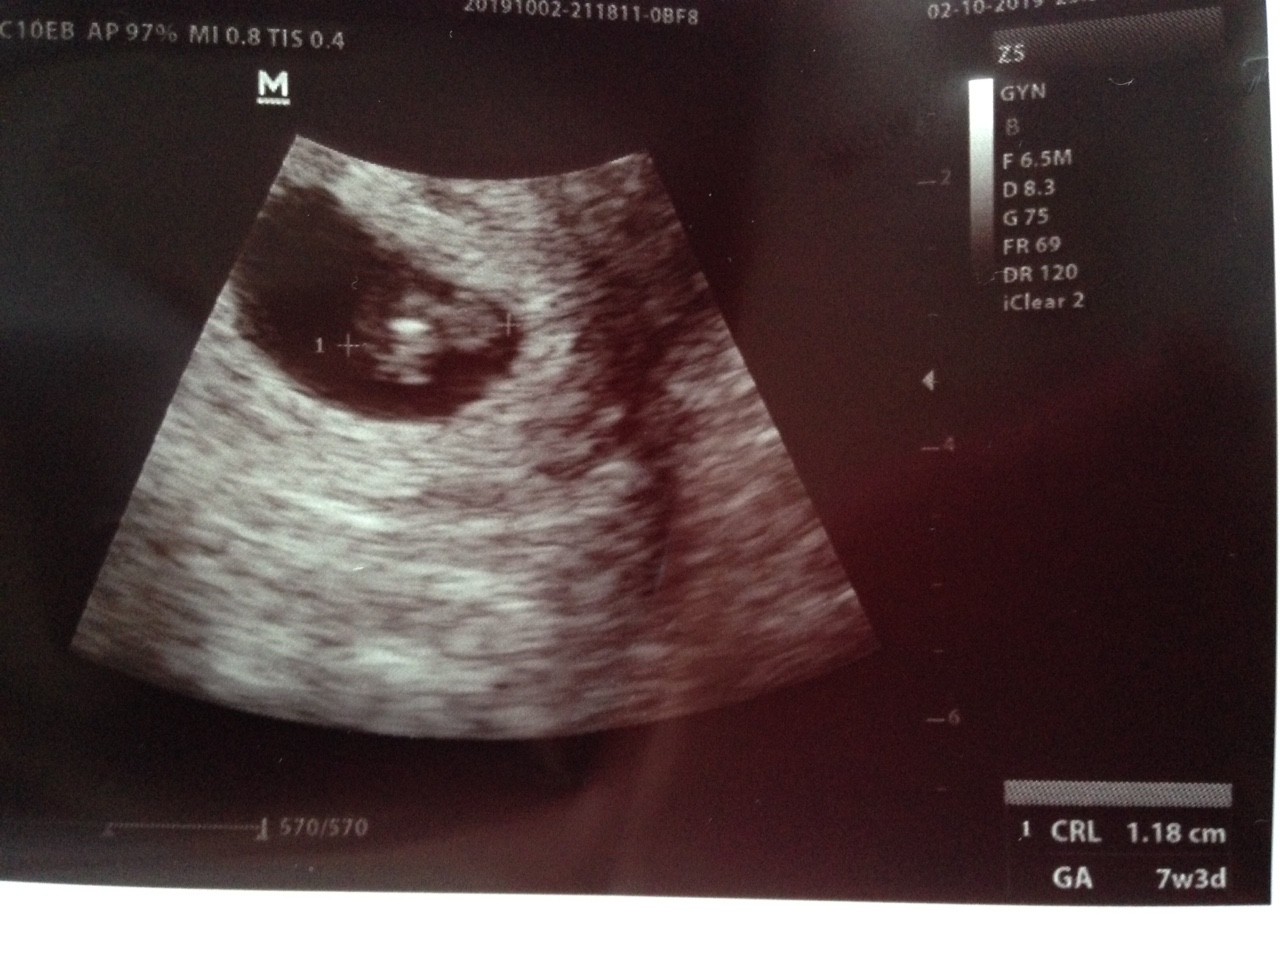

Już po wizycie! Jest czynność serca Puls 145 na minutę. Od ostatniej miesiączki jestem w 6+3 A według usg to 7+3.

Zrozumiałam że mój Maluszek ma 7 mm ale teraz na usg widzę CRL 1,18.

PS. Ta biała plamka to serduszko

Zobacz załącznik 1029344